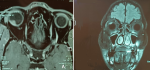

Démarche diagnostique: l'angiographie à la fluorescéine a montré une lésion hypo-fluorescente au temps précoce, devenant hyper-fluorescente au temps tardif, avec persistance d'un centre hypo-fluorescent (Figure 1 B). L'échographie oculaire (Figure 2) ainsi que l'imagerie par résonance magnétique (Figure 3) ont révélé une masse choroïdienne, saillante, en dôme ou en champignon, bien limitée para-maculaire supérieure, compatible avec une tumeur intraoculaire. Les caractéristiques qui ont été rapportés sont: masse tissulaire hyperéchogènes, hétérogène, de contours nets, hypervascularisée, siégeant à droite du nerf optique, mesurant 7x7 mm.

Figure 3: imagerie par résonnance magnétique cérébro-orbito-oculaire: A) coupe horizontale; B) coupe sagittale montrant une masse intraoculaire droite